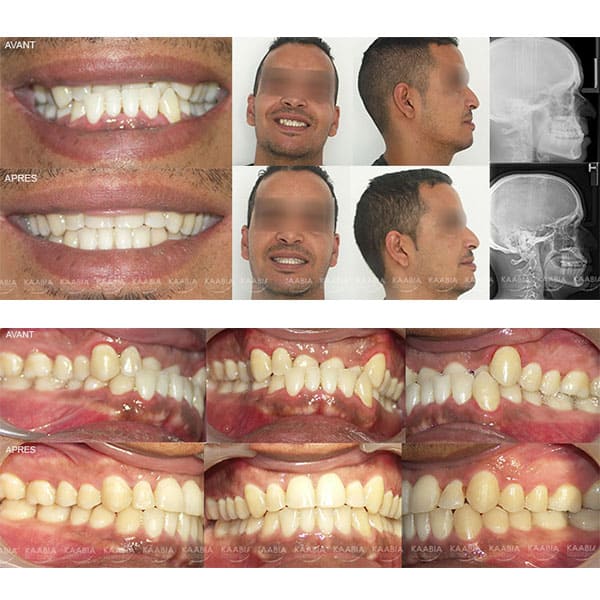

Traitement des retroalvéolies supérieures